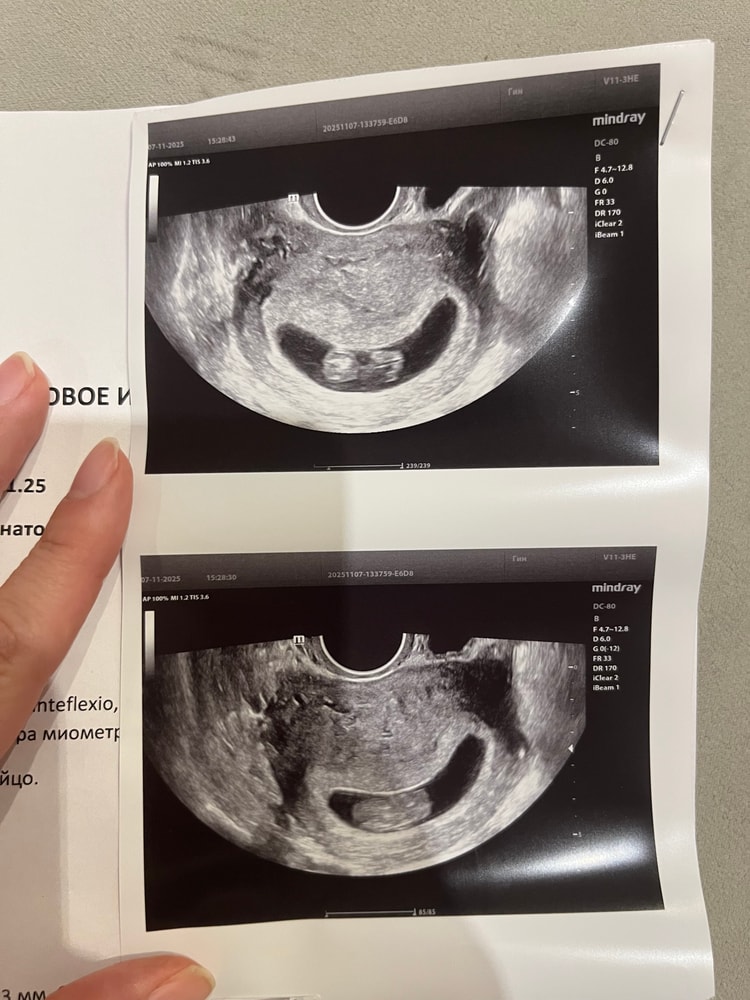

УЗИ 9+1

УЗИ, КТГ, доплерДевочки, переживаю, ходила сегодня на узи, все ли хорошо? ПЯ такое вытянутое и размер странный 😞

Мне говорили о тонусе при таком яйце, но в то же время говорили, что для срока норм и оно станет нормальным. Попила магний и всё ок было